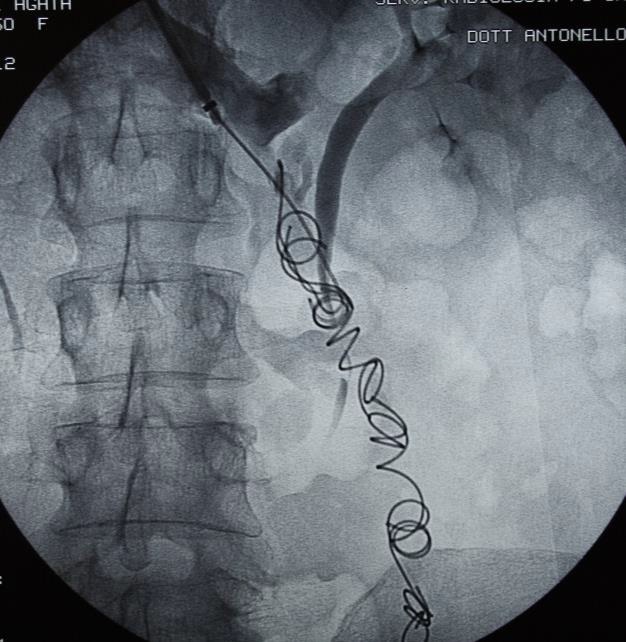

Embolization of Ovarian Vein Varices

Embolization 材料包括

• Coils

• Sclerosing agent

• Glue

• Combination

1: Coïls only 2: Coïls + Foam 3: Coïls + Onyx

No. Coil 7.2 coils (2-21), 4 coils (1-15), 4 coils (2-10)

Average time procedure > 60 min < 45 min 60 min

Transitory pelvic pain (< 48 h): 5% 5% 2%

Transitory variation of temperature (38°C): yes yes -

Pain during the procedure 1 % 12 % (spasm and foam) 100 %(DMSO)

Bad Breath (Smell of garbit during 2 days): - - yes

migrating coils (without consequence) 2 1

pulmonary embolismce): (without consequence) 1 1

vision trouble (foam)q   1

Recurrence of SCP and/or SCVI(follow up) 8 % at 9 years 3 % at 5 years too short

cost the same the same more expensive